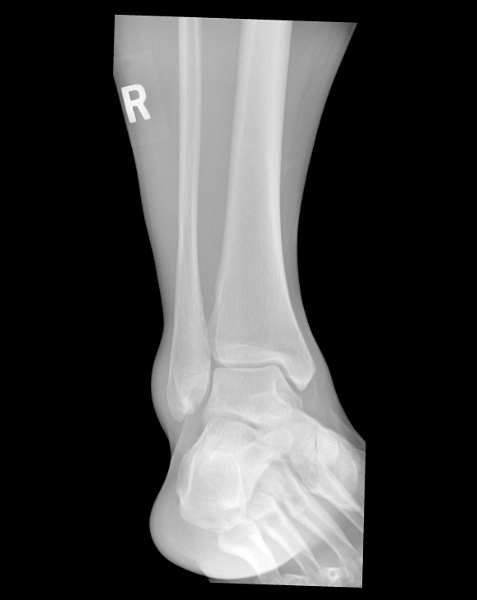

Ankle (1) Ankle (1) Ankle (2) Ankle (2) Ankle (3) Ankle (3)

Ankle (4) Ankle (4) Ankle (5)